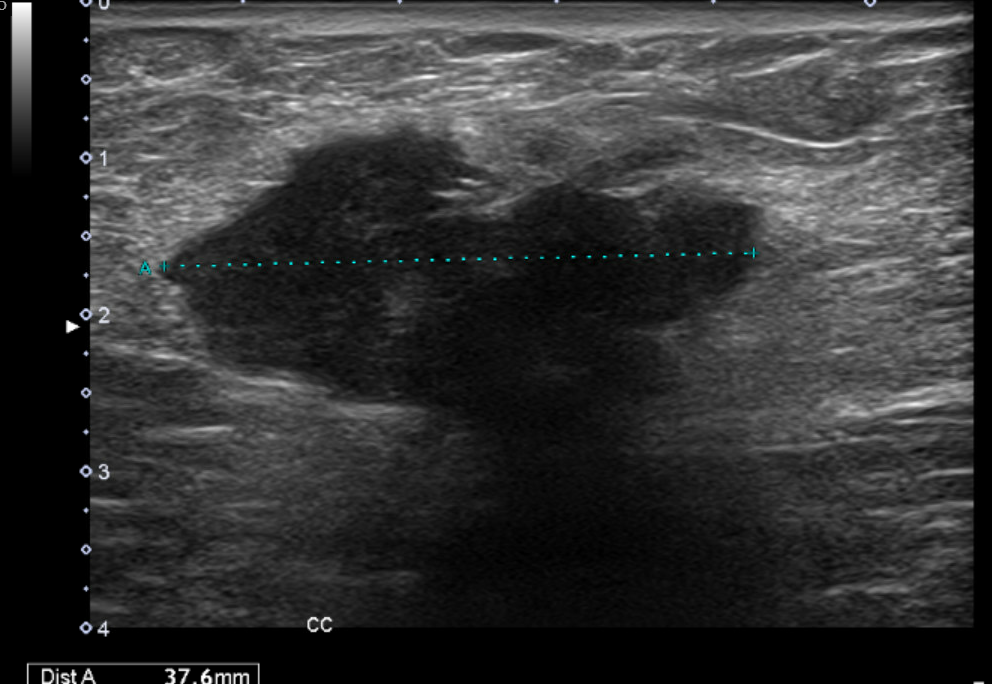

Ecografía clínica partes blandas y abdominal en Centro de Salud: dos nódulos subcutáneos hipoecogénicos, heterogéneos, lobulados y de bordes irregulares (16 x 18 mm), no vascularizados. Abdomen: sin signos patológicos relevantes ni Ascitis ni líquido en Douglas no adenopatías retroperitoneales. Completamos estudio de nódulos sospechosos de malignidad con tomografía abdominal y ecografía de partes blandas reglada.

Ecografía reglada de partes blandas: Nódulos subcutáneos e intrabdominales sospechosos de malignidad. La tomografía abdominal describe múltiples implantes sólidos peritoneales y en pared abdominal, compatibles con metástasis.

El Comité multidisciplinar de tumores decide Biopsia guiada por ecografía + PET/TC que confirma múltiples implantes hipermetabólicos. Biopsia: Carcinoma de endometrio con pérdida de expresión de PMS2 y MLH1, confirmando la naturaleza metastásica del nódulo umbilical. Tratamiento con citoreducción e Inmunoterapia.